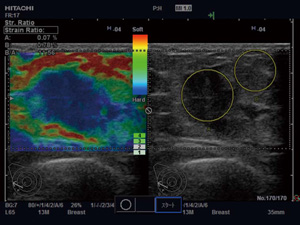

3.Strain Ratio

Elastography画像において,任意の2か所の比を数値で表示ことができる。例えば,乳腺領域では脂肪組織と関心領域の比(Fat Lesion Ratio:FLR)を求めることができ,組織性状の研究などへの応用が期待されている(図9)。 |

図9 FLR(乳腺) |